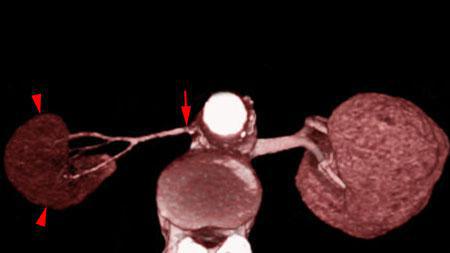

Infartos renales múltiples